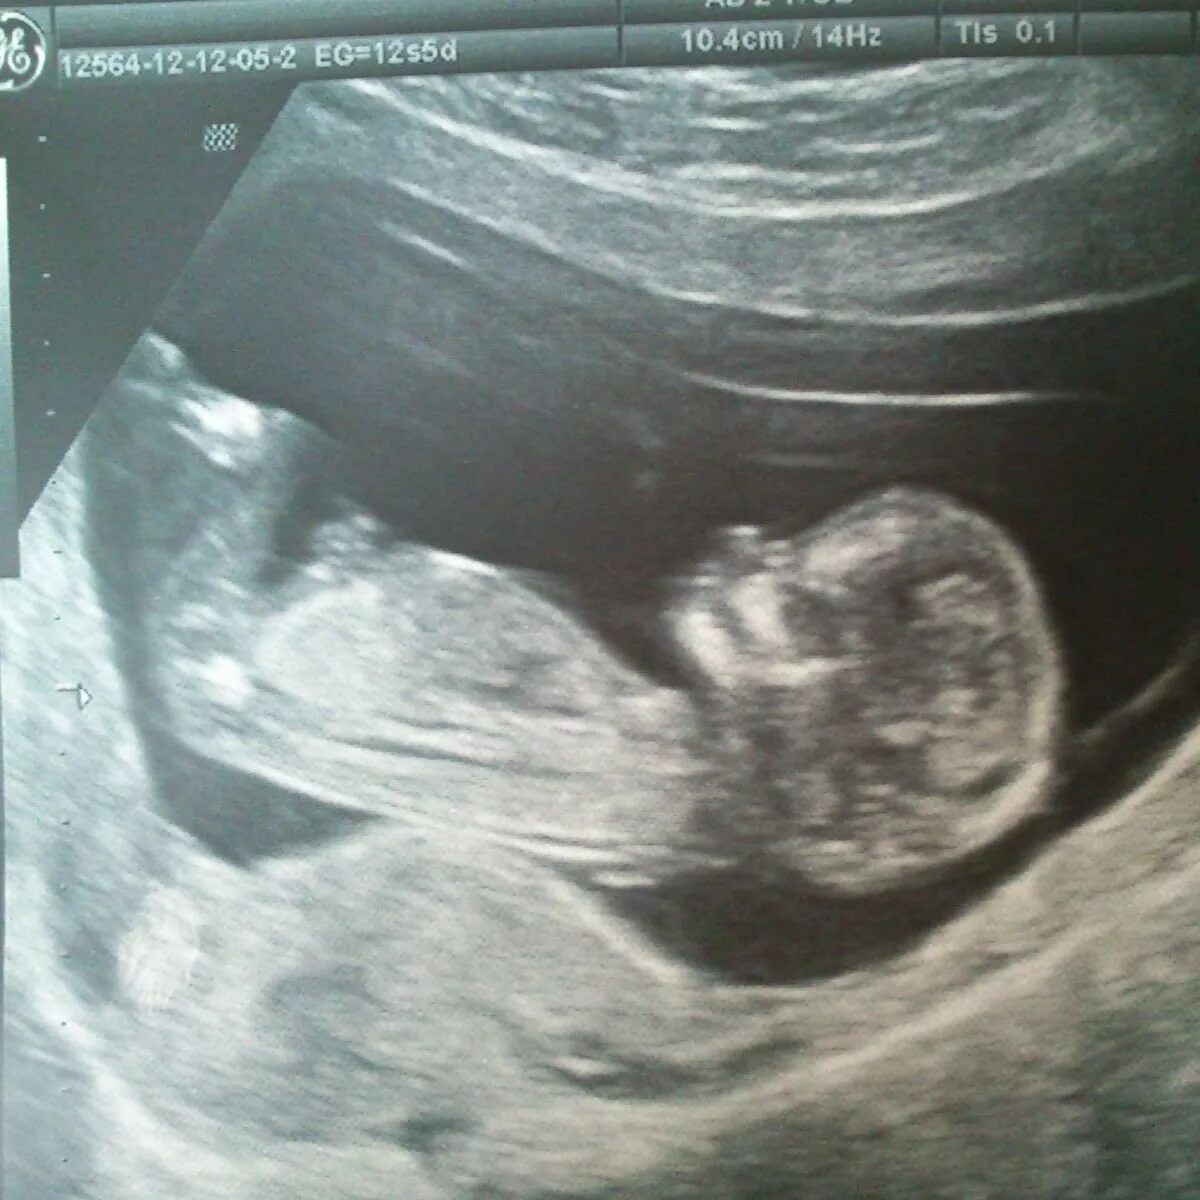

7 12 недель